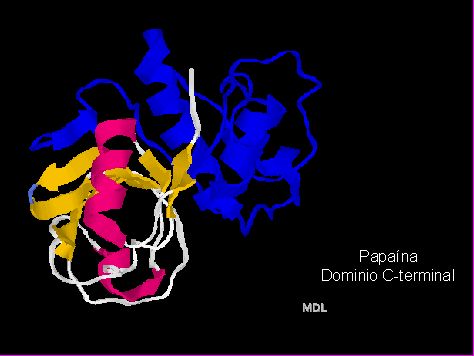

Como otro componente dentro del sistema químico-mecánico de remoción de tejidos cariados surge el Papacárie® en el 2003, UNINOVE (Universidad de São Paulo/Brasil), como un mecanismo de proteolisis enzimática del colágeno dentinario. Este producto está compuesto por Papaína, cloramina, azul de toluidina, conservante, espesante y vehículo. La enzima Papaína es una tiol-proteinasa, es decir, una enzima proteolítica cuyo centro activo posee un grupo -SH- . Se extrae del látex de la papaya o mamao verde (Carica papaya), es la responsable de las conocidas propiedades digestivas de dicha fruta y es empleada ampliamente en la industria alimenticia, farmacéutica y cosmética.

En la estructura de la Papaína (Figuras 13 y 14)11 se aprecian dos "ovillos" (dominios) separados por una zona sin estructura secundaria en particular. Así, el dominio 1, que corresponde aproximadamente a la mitad N-terminal de la molécula, presenta una estructura secundaria de tres alfa-hélices, mientras que el dominio 2 o C-terminal: tiene una estructura secundaria distinta (un meandro b antiparalelo y dos a-hélices). A menudo los dominios corresponden a diferentes funciones dentro de la misma proteína (por ejemplo, regiones catalíticas y regiones regulatorias) y casi siempre corresponden a tramos genéticos codificantes (exones) diferentes.

Fig. 14

La Papaína se identifica como una endoproteasa. Las proteasas con tiol (Stryer L.)12 ,13 son un grupo de enzimas ampliamente distribuido, que contiene un centro activo con cisteína, la cual realiza una función análoga a la de la serina 195 de la quimotripsina. La catálisis se realiza a través de un intermediario tioester y se halla facilitada por una cadena lateral de histidina próxima. Presenta propiedades: antiinflamatoria, bacteriostática y bactericida (Candido, 200114 ;Pereira, 2004 15).

Particularmente, la papaína es una tiol proteasa cuyo centro activo es Cis 25, His 159, y Asp 15816. Presenta una amplia actividad proteolítica ante las proteínas, péptidos de cadena corta, enlaces amida y ésteres de aminoácidos y se utiliza de manera muy extendida en el ámbito de la alimentación y la medicina. Su peso molecular es de 23,000 dalton y su pH óptimo es entre 3 y 7 el cual varía según el sustrato. Su número de clasificación es 3.4.22.2. Pertenece a la clase de las hidrolasas, tiene una amplia especificidad sobre las uniones peptídicas siendo una endopeptidasa (rompe enlaces peptídicos de sus sustratos que no están cerca de los extremos terminales de la proteína a romper).